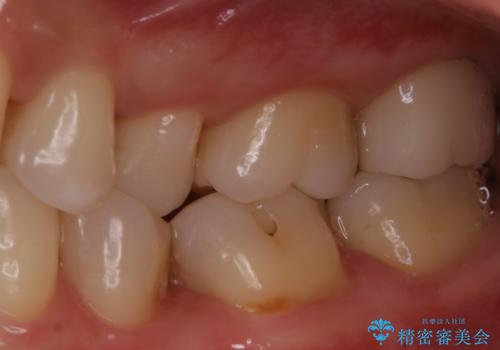

- 一番奥の歯に違和感がありご来院頂いた患者様です。

診断の結果、一番奥の歯は失活していたため精密根管治療から治療介入となりました。奥から2番目の歯にも大きな虫歯が認められたため、セラミックインレーによる補綴治療を行いました。 精密根管治療は患者様のご希望により、福本院長に行っていただきました。

セラミックは強い咬合力がかかると割れてしまうリスクがあります。今回のケースでは、歯を削る量をなるべく少なくしたいとの患者様の強い希望により、セラミックインレーを作製しました。破折してしまった場合には、歯牙全体を覆うクラウンにすることを十分説明し、ご理解いただいたうえで装着しております。